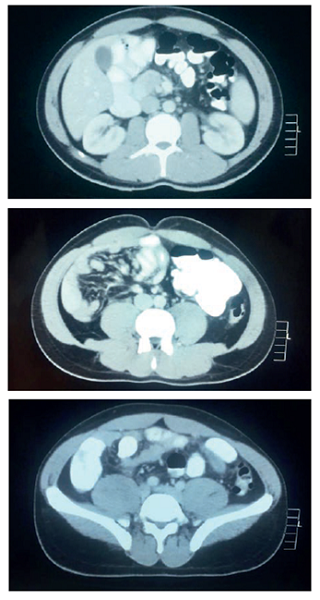

Durante el seguimiento, tres meses después, el paciente presentaba dolor torácico ocasional, esporádico y de intensidad moderada, razón por la cual se practicó una ecocardiografía transesofágica y se observó insuficiencia valvular aórtica moderada secundaria a una válvula aórtica bivalva sin estenosis (figura 3).